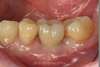

REMPLACEMENT D'UNE DENT (MOLAIRE) PAR UN IMPLANT DENTAIRE